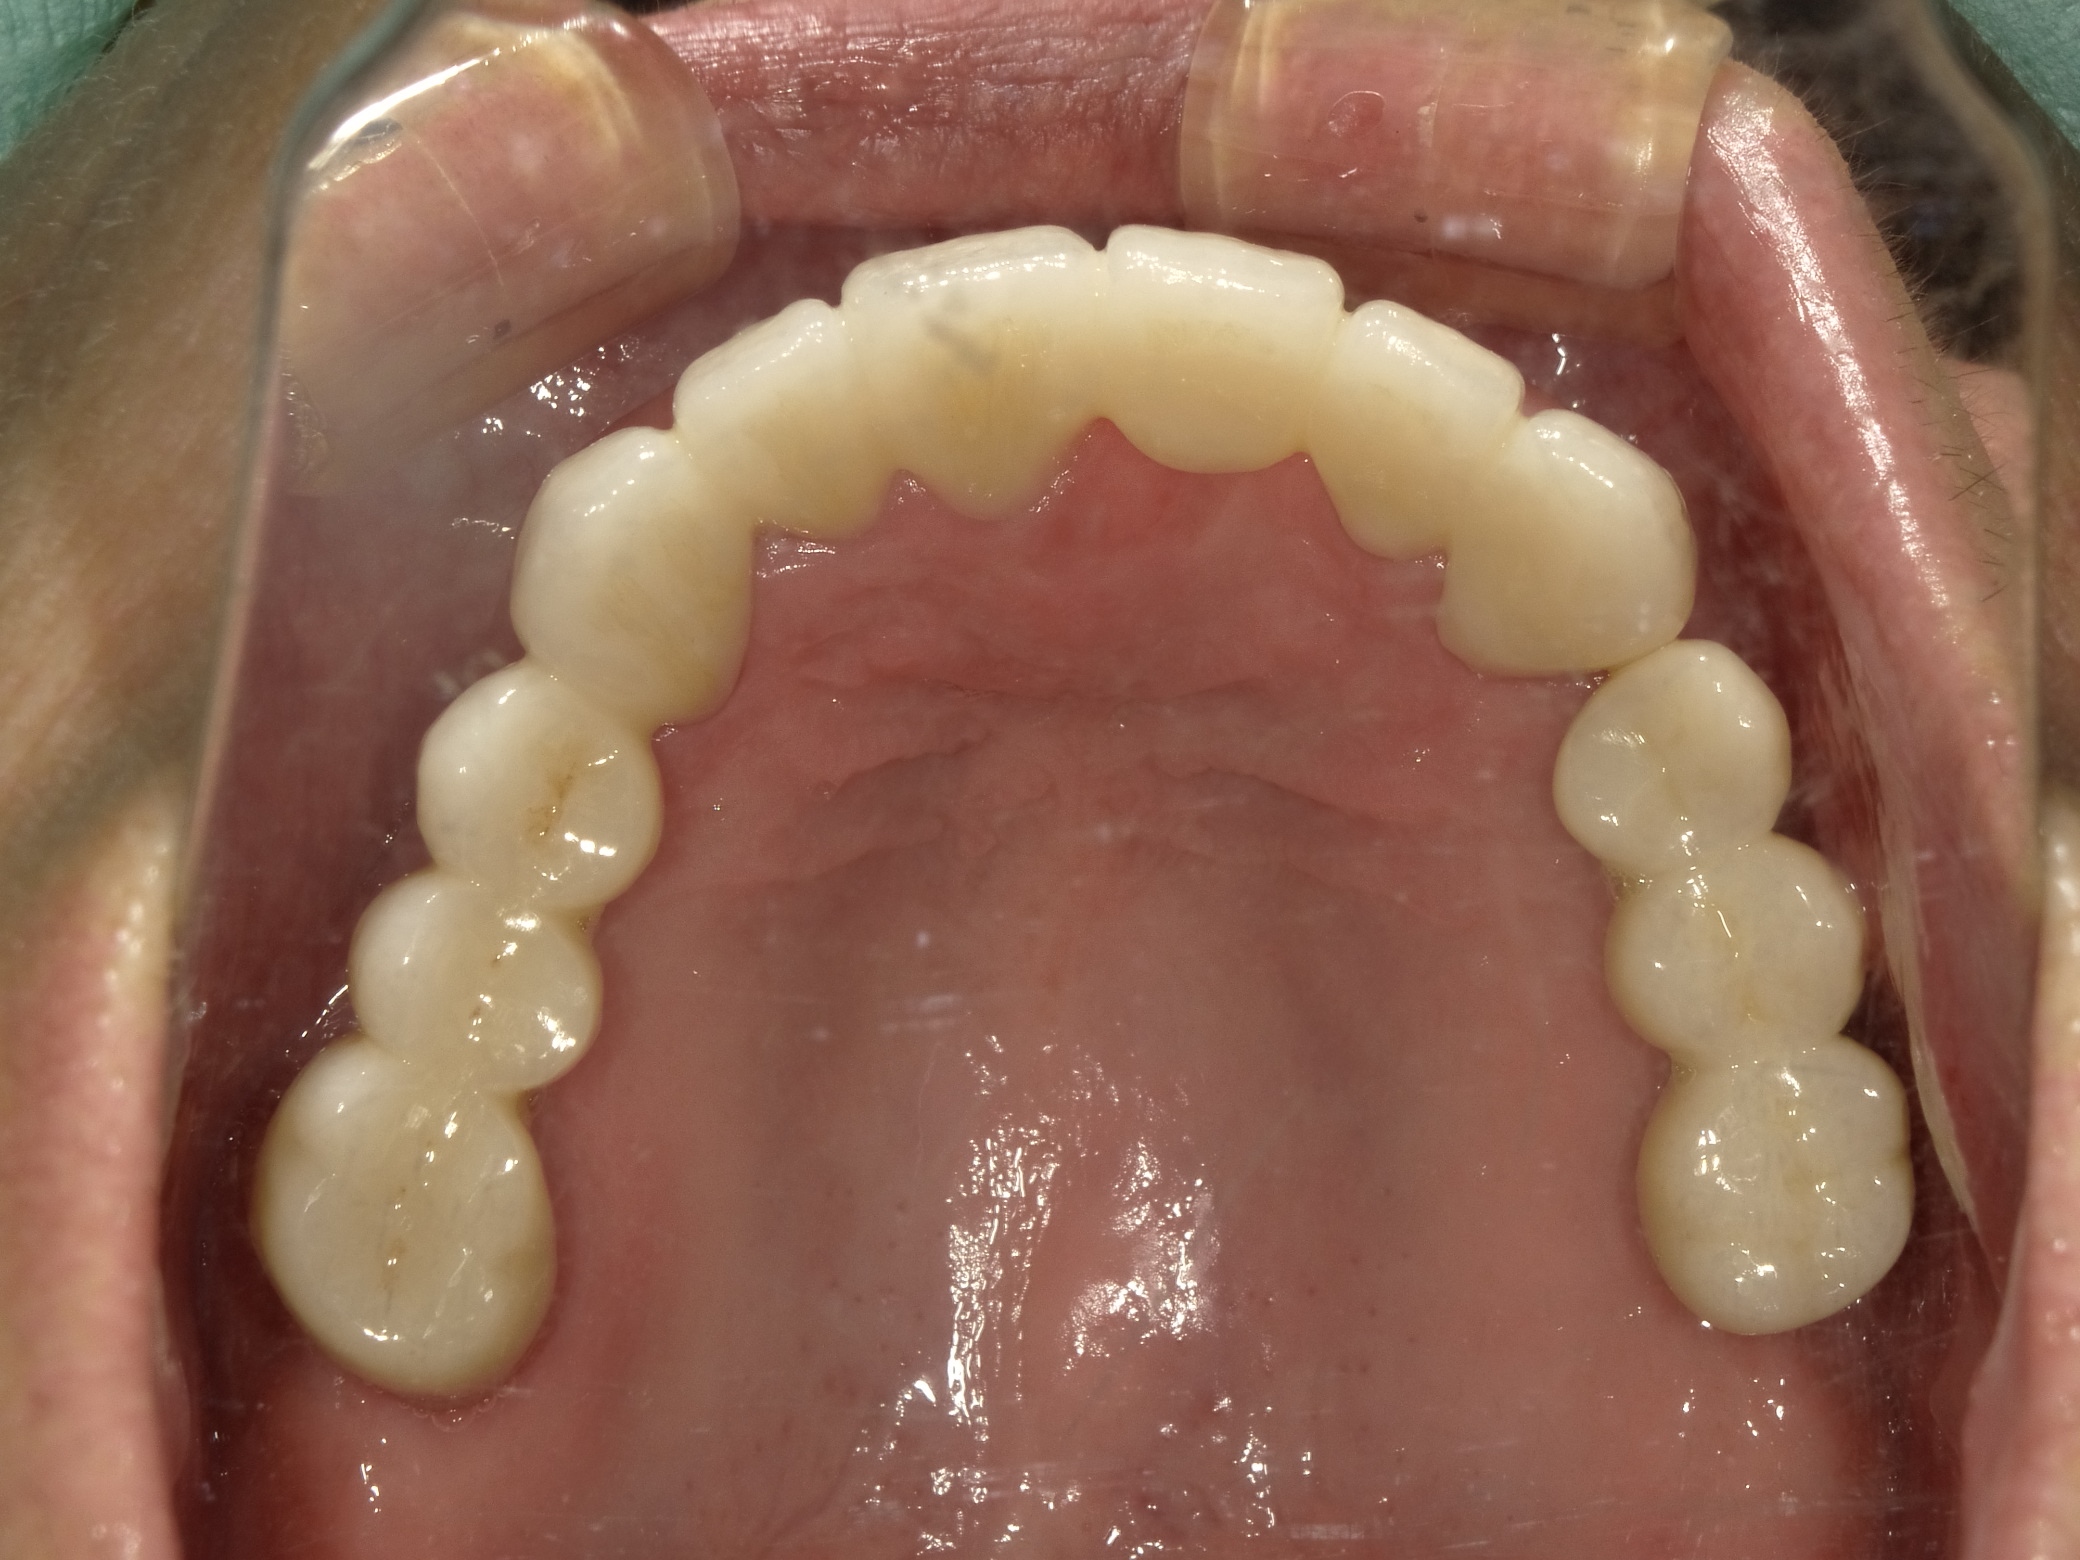

AFTER

主訴

全体的に見た目を綺麗にしたい。奥歯でしっかり噛みたい。

診断名・主な症状

臼歯部欠損

年齢

65歳

治療内容

インプラント埋入(左下5・6,右下5・6,左上4・6)

サイナスリフト(左上4・6)

ジルコニアBr(右上6−左上3)

E –MAX CAD(右下4)

セラミックインレー(左下4)

治療期間/

約1.5年/約20回

インプラント治療 約2,000,000円

その他被せ物治療など 約1,000,000円

合計 約3,000,000円